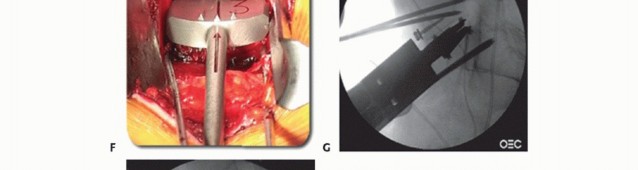

In cases of corpectomy for vascular tumors, preoperative embolization should be performed (TECH FIG 6A).

In cases of corpectomy, radical discectomies are performed above and below the vertebral body to be removed (see discectomy technique discussed earlier).

This enables the surgeon to become oriented to the midline and also to judge the depth and width of the corpectomy to be performed.

The discectomy space also allows the surgeon to use a large rongeur efficiently to remove the vertebral body (TECH FIG 6B).

- TECH FIG 6 • A. Preembolization angiogram depicting the aortic bifurcation in a 65-year-old patient with metastatic renal cell carcinoma to the L4 vertebra. Note the degree of vascularity of the L4 vertebral body.

- B. Postembolization angiogram depicting a striking reduction in contrast entering the L4 vertebral body. Small embolization coils are seen in the vascular network surrounding the vertebral body. C. Anterior discectomy enables the surgeon to use a large rongeur to gain access to the edge of the vertebra and thereby remove the vertebral body bone.

Metal cages generally are the easiest to fashion to fit the corpectomy space and can be packed with morselized corpectomy bone (TECH FIG 7A). The disadvantages are their expense and relatively reduced surface area at the endplate for fusion compared to bone.

The width of the corpectomy should be kept as narrow as possible without compromising decompression or removal of pathologic bone (TECH FIG 7B).

A bone screw with a washer can be used above and below large defects as an “anti-kickout” buttress for allografts (TECH FIG 7C).

Allograft strut grafts such as femoral head, humerus, or fibular shafts can be cut using an oscillating saw to fit snugly into the interbody space (TECH FIG 7D). The advantages of allograft are it can be packed with morselized autogenous bone, it has a similar modulus of elasticity to host vertebral bone, and it will become osseointegrated over time.

Expandable corpectomy devices have been developed to facilitate anterior column reconstruction following single- or multilevel corpectomy. These devices are inserted and expanded until there is good interference fit at the endplates (TECH FIG 7E).